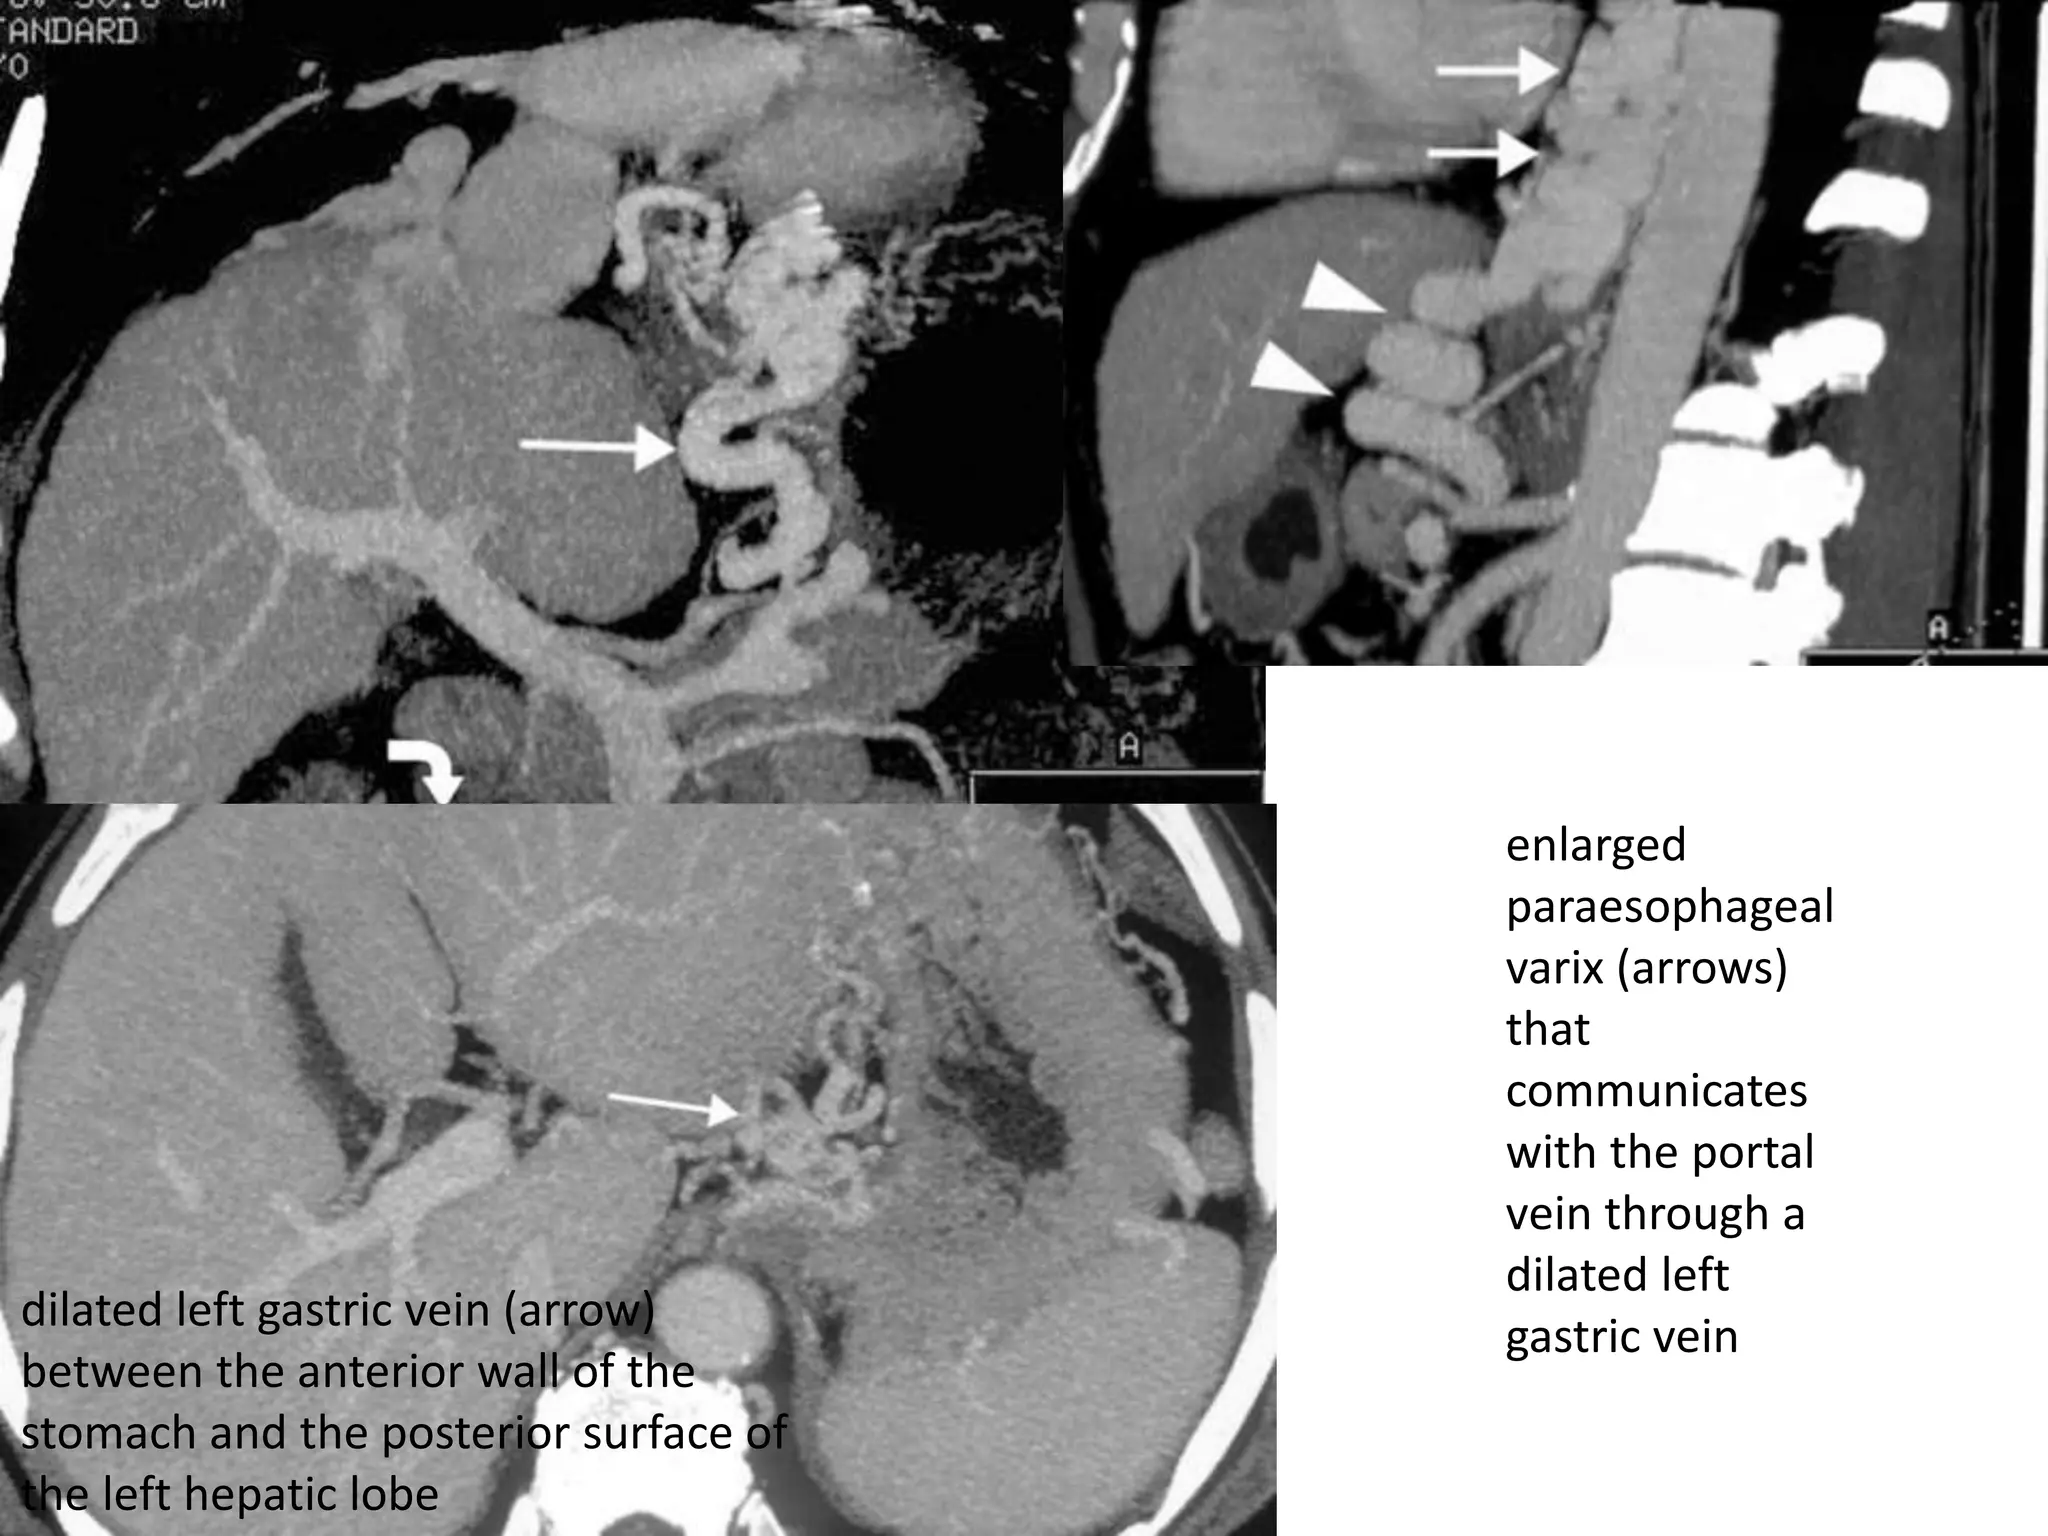

enlarged

paraesophageal

varix (arrows)

that

communicates

with the portal

vein through a

dilated left

gastric vein

dilated left gastric vein (arrow)

between the anterior wall of the

stomach and the posterior surface of

the left hepatic lobe